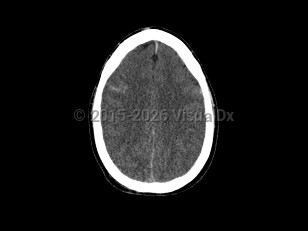

PapilledemaPapilledema